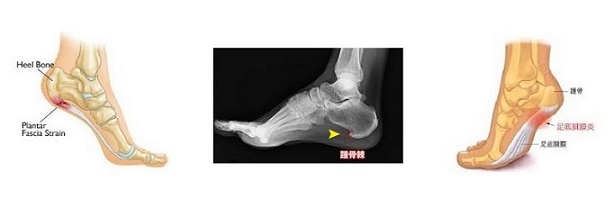

3日4日5日... と経過しても朝一番の激痛は変わらない、昼を回る頃に痛みは少し引く、骨の損傷はないと考えられたが、なかなか回復しないので1週間後ついに病院に行くことにした。整形外科でX線エコー検査を受け、骨は問題なく踵骨棘付近の腱膜に炎症が起こっている ” 足底腱膜炎 ” と診断され、低周波治療と痛み止め湿布を処方された。診断がついたのでひとまず安心はしたが、原因は間違いなくあのタイマッサージだ。既に帰国していた身でもあり、不運を嘆くしかなかった。ただ今にして思えば自分が受け取るべきカルマであったのかとも思える。故事曰く、「カルマはカルマによってのみ拭い取れる」と云う